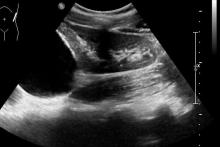

Pacjentka została przyjęta do Szpitala, wykonano nieskuteczną próbę odgłobienia wlewem wodnym pod kontrolą USG (biała strzałka - wgłobienie, pomarańczowe strzałki - płyn w jelicie grubym). Pacjentka operowana - stwierdzono wgłobienie patologiczne, z uchyłkiem Meckela jako punktem prowadzącym.